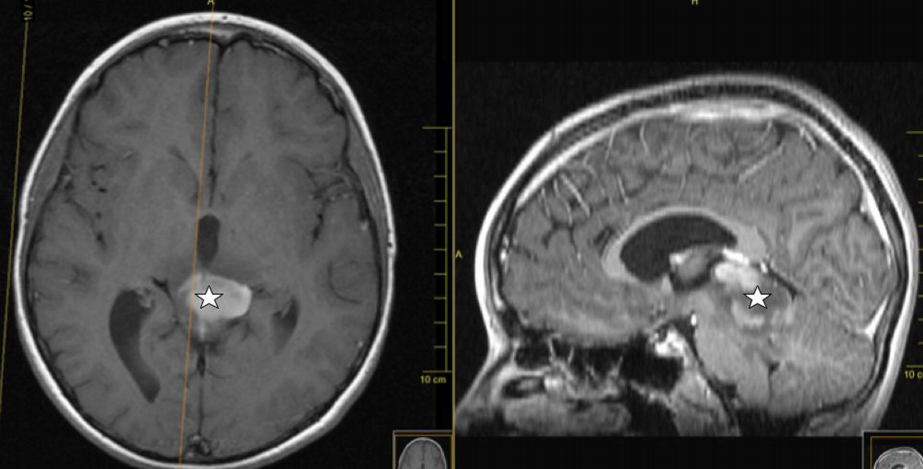

一名11歲男童因診斷為四叉神經(jīng)板中線腫瘤而入院,癥狀為因雙側(cè)外展神經(jīng)麻痹引起的頭痛和復(fù)視。檢查發(fā)現(xiàn)雙側(cè)乳頭水腫。頭部MRI顯示一個(gè)中線病變,圍繞頂蓋區(qū),從小腦向松果體延伸,侵犯間腦(圖1和2)。

圖1。術(shù)前矢狀t2加權(quán)磁共振成像顯示從小腦延伸到丘腦的四頭神經(jīng)板高信號病變(星型)

圖2。術(shù)前軸位和矢狀位的t1加權(quán)磁共振圖像顯示部分增強(qiáng)的四叉神經(jīng)板低信號病變(star)和雙側(cè)丘腦受累